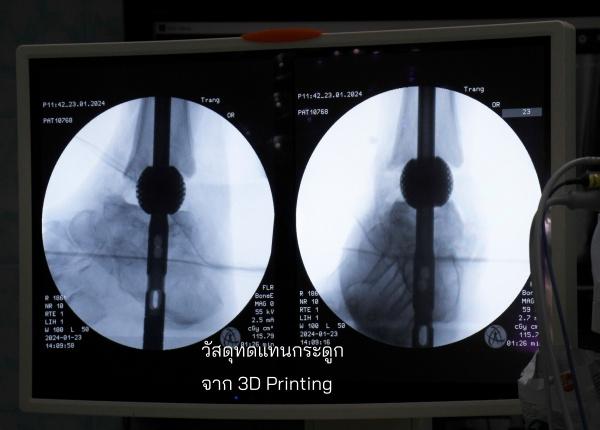

มหาวิทยาลัยเทคโนโลยีพระจอมเกล้าธนบุรี (มจธ.) เปิดตัวนวัตกรรมวัสดุทดแทนกระดูกพรุนพิมพ์ด้วยเทคโนโลยีสามมิติ จากการออกแบบโครงสร้างวัสดุพรุนจากกระบวนการพิมพ์สามมิติ เพิ่มคุณสมบัติเชิงกลและเชิงชีวภาพสำหรับเป็นวัสดุทดแทนกระดูก พัฒนาระบบวางแผนการผ่าตัดแบบดิจิทัลและกระดูกเทียมเฉพาะบุคคล สำหรับศัลยกรรมกระดูกและใบหน้า ด้วยเทคโนโลยีการพิมพ์สามมิติและปัญญาประดิษฐ์ (Artificial Intelligence: AI) พัฒนาโดยทีมวิจัย มีรศ. ดร.พชรพิชญ์ พรหมอุปถัมภ์ อาจารย์ภาควิชาวิศวกรรมเครื่องกล คณะวิศวกรรมศาสตร์ มหาวิทยาลัยเทคโนโลยีพระจอมเกล้าธนบุรี (มจธ.) และ ผู้บริหารระดับสูงด้านเทคโนโลยีและนวัตกรรม (Chief Technology Officer : CTO) บริษัท ออสซีโอแล็บส์ จำกัด ธุรกิจที่แยกตัว (Spin-off) ของ มจธ. เป็นหัวหน้าโครงการฯ เป็นการบุกเบิกในวงการศัลยกรรมกระดูก นวัตกรรม เพื่อแก้ไขข้อจำกัดการรักษาแบบดั้งเดิม โดยเฉพาะปัญหาการติดเชื้อซ้ำสูง ช่วยให้กระดูกของผู้ป่วยยึดติดกันได้ดี มีความแม่นยำทางกายวิภาคของวัสดุทดแทนกระดูกที่ใช้กันทั่วไปจากเดิมที่ใช้ กระดูกบริจาคหรือซีเมนต์ทางการแพทย์

รศ. ดร.พชรพิชญ์ กล่าวว่างานวิจัยนี้สะท้อนความสำเร็จทางการแพทย์ในเคสที่มีความท้าทายสูง อาทิ ผู้ป่วยข้อเท้าเสื่อมที่มีภาวะกระดูกติดเชื้อจากโรงพยาบาลตรัง และผู้ป่วยกระดูกหักที่กระดูกไม่ติดกันจากอุบัติเหตุในโรงพยาบาลสงขลานครินทร์ ทั้งหมด 7 ราย ประสบความสำเร็จในการรักษา กลับมาเดินได้ตามปกติ แสดงว่าวัสดุหรืออุปกรณ์ที่พัฒนาขึ้นปรับใช้กับกระดูกได้หลากหลายชิ้นทั่วร่างกาย

จุดเด่นของนวัตกรรม คือKnow-how การออกแบบกระดูกเทียมเฉพาะบุคคลให้เป็นอุปกรณ์ทางการแพทย์ที่ใช้งานได้ดี เหมาะสมกับแผนการรักษาที่แพทย์วางไว้และใช้งานได้จริง ประกอบกับโครงสร้างวัสดุพรุนที่ทำจาก 3D Printing เป็นตัวเข้ามาเสริมการเกาะของกระดูก เข้าใจ Pain Point ของแพทย์